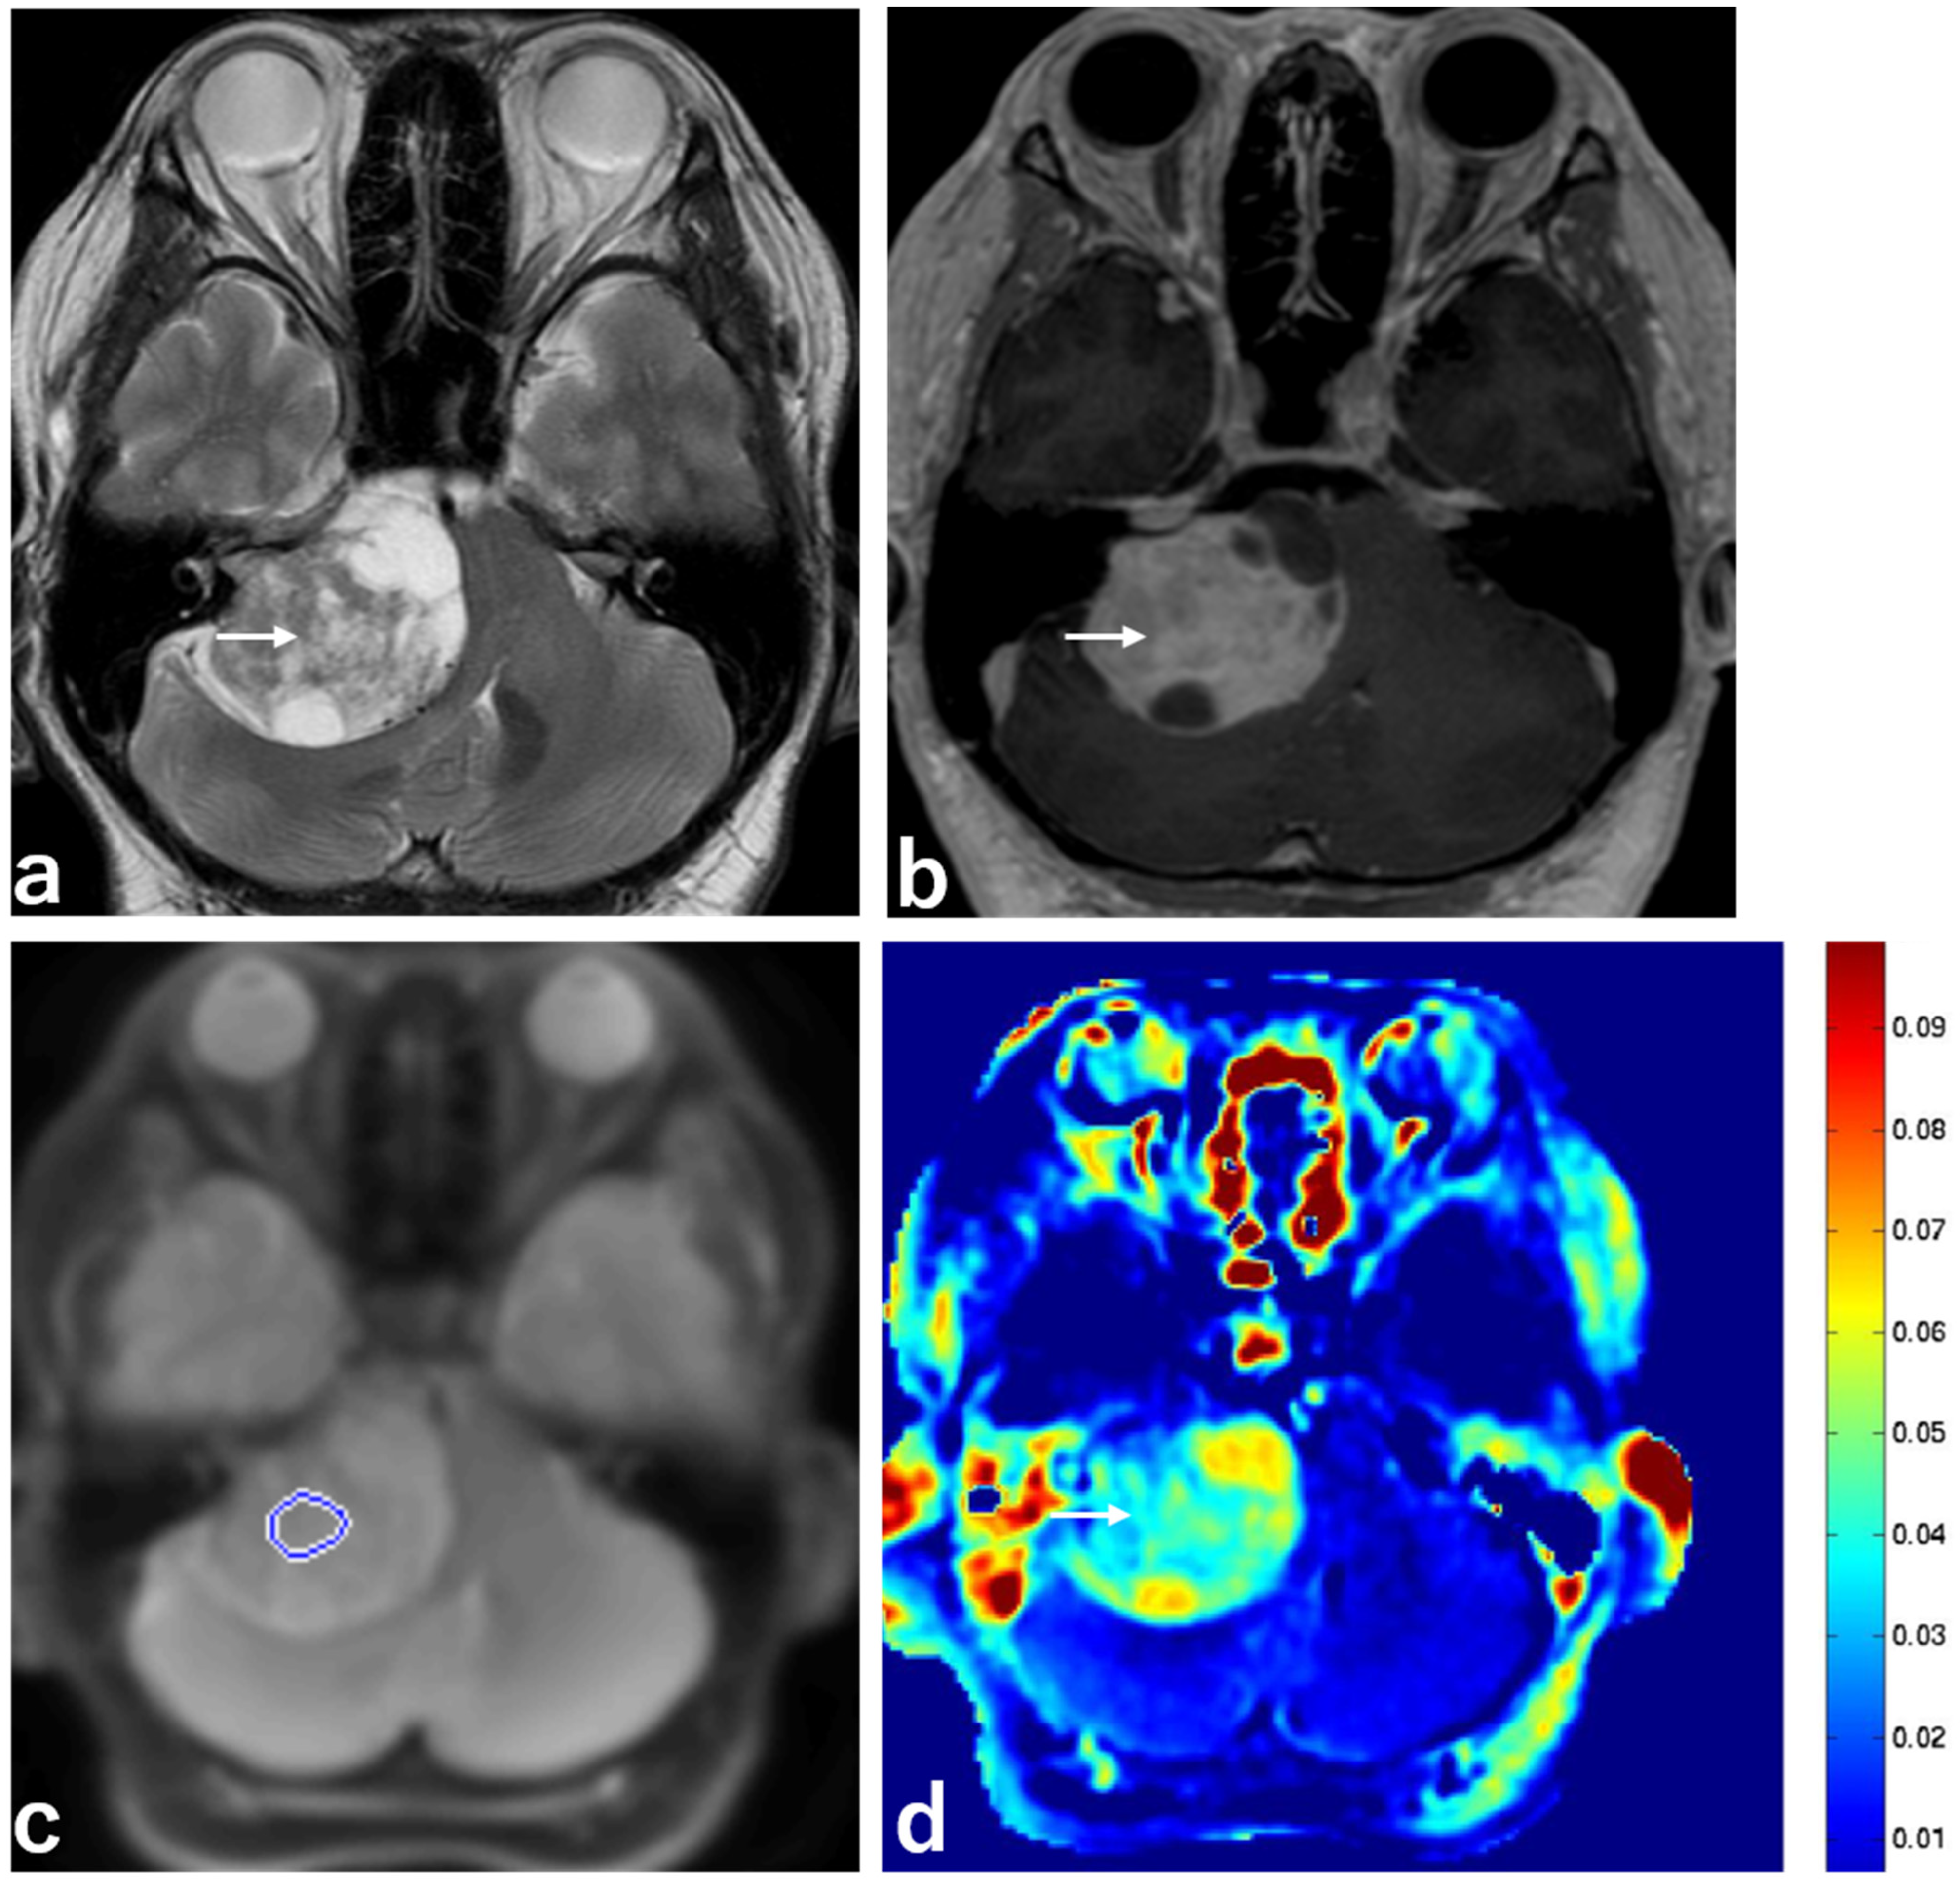

| Mean MTRasym | 0.033 ± 0.012 | 0.021 ± 0.004 | 0.007 |

| T2 hyperintensity | 6 (66.7%) | 2 (22.2%) | 0.058 |

| Heterogeneous enhancement | 6 (66.7%) | 2 (22.2%) | 0.058 |

| Variable | Schwannoma with Hyperintensity (n = 6) | Schwannoma with Low Intensity (n = 3) | p |

| Mean MTRasym | 0.039 ± 0.006 | 0.021 ± 0.008 | 0.014 |

| Heterogeneous enhancement | 6 (100%) | 0 (0%) | 0.003 |